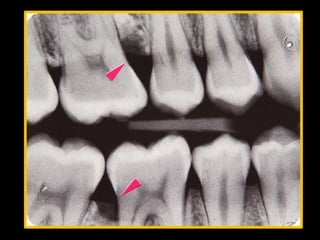

Classic diagnostic sign:

Vertical loss of alveolar bone around 1st

molars & incisors

Beginning around puberty in an otherwise

healthy teenagers

―Arc shaped loss of alveolar bone

extending from distal surface of 2nd

premolar to mesial surface of second

molar‖

Clinically, localized juvenile periodontitis (LJP)

patients rarely show calculus or plaque formation

and often exhibit little or no gingivitis.

However, deep probing, attachment loss,

radiographic bone loss are found. Deep

interproximal vertical bone loss on first molars

and incisors are characteristic of LJP. Juvenile

periodontits should be identified and treated

early with antimicrobial therapy, scaling and

root planing, and also surgery according to

extent of destruction.